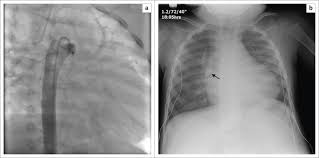

Icd Vs Pacemaker Cxr : Chest X Ray Of The Patient Showing The Pacemaker In Situ And The Download Scientific Diagram / The pacemaker is the steady hand guiding your heart through each day, while the defibrillator is the guardian angel standing ready to keep you safe if your.. Here an example of an icd with wires in the right atrial appendage, the apex of the right ventricle and a lead to the left ventricle in the posterior coronary vein. They are now what make the heart beat normally because our own muscles cannot do that anymore. Fixed (asynchronous) pacing carries risk of r on t, however, there is little outcome data to support a preference for either. The purpose of this article is to review the normal and abnormal radiographic appearances of cardiac pacemaker and implantable cardioverter defibrillator systems. Now there is a solution courtesy of the em rems blog:

It works very much like a pacemaker. Implantable cardiac conduction devices (also known as cardiac implantable electronic devices or cieds) are a very common medical device of the thorax, with over one million implanted in the united states of america alone. Anesthesia professionals should know what type of device the patient has (pacemaker vs. There are 2 leads connected to the icd that course through the central veins in the chest to the heart. I have been competively swimming for 12 years. The purpose of this article is to review the normal and abnormal radiographic appearances of cardiac pacemaker and implantable cardioverter defibrillator systems. They are now what make the heart beat normally because our own muscles cannot do that anymore. Now there is a solution courtesy of the em rems blog: In 2009, more than 300,000 adults and children in the united states underwent placement of a new pacemaker or icd, and over 150,000 patients underwent revision .all u.s. Look for any sign of infection, ask for u/a, blood cx's, cxr if there is any question. If not identifiable, then proceed to step 4. Case discussion note the slightly larger control box of the implantable cardiac defibrillator when compared to a normal permanent pacemaker. Dual lead icd projects over the left chest.

Chest radiographs showing pacemakers and implantable cardioverter defibrillators contain identifying and clinically relevant information, such as mri compatibility and. Difference between icd and pacemaker while both the icd and pacemaker deal with matters of the heart, they have different functions. Case discussion note the slightly larger control box of the implantable cardiac defibrillator when compared to a normal permanent pacemaker. Nice little tip from the emergency board review videos: In 2009, more than 300,000 adults and children in the united states underwent placement of a new pacemaker or icd, and over 150,000 patients underwent revision .all u.s.

This is called resynchronization pacing. Almost all icds these days also come with pacemaker capabilities as well. The first day i swam in the 800 meter freestye. There are 2 leads connected to the icd that course through the central veins in the chest to the heart. It works very much like a pacemaker. They are now what make the heart beat normally because our own muscles cannot do that anymore. Nice little tip from the emergency board review videos: Magnets placed over icds affect only the tachycardia sensing function! If not identifiable, then proceed to step 4. Pacemakers have a more regular function; Difference between icd and pacemaker while both the icd and pacemaker deal with matters of the heart, they have different functions. Case discussion note the slightly larger control box of the implantable cardiac defibrillator when compared to a normal permanent pacemaker. The only way to affect pacemaker function on an icd is with a programming device